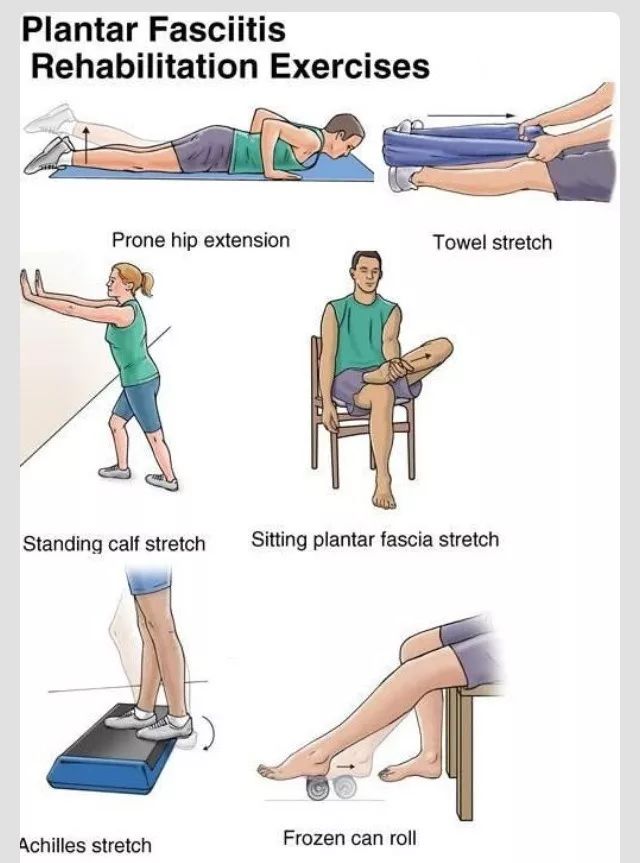

大多数有足底筋膜炎的人在几个月的保守治疗后可以恢复。这些治疗包括休息、冷敷痛点、伸展运动来舒展足底筋膜和跟腱、力量训练等理疗来加强小腿肌肉的力量,稳定你的脚踝和脚后跟。理疗师也可能教你使用运动贴布来支撑你的脚底。可以试试下面这些动作。很管用哦!

拉伸运动来舒展筋膜

加强小腿肌肉和跟腱的力量

拉伸运动

舒展筋膜